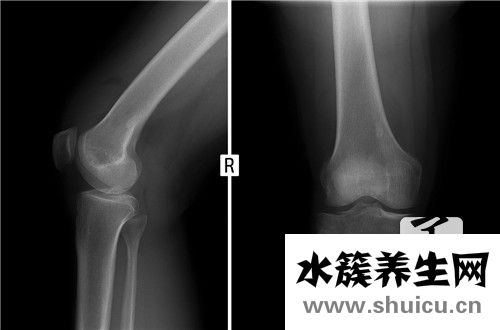

腓骨perone系下肢小腿肚長骨之一。偏細,在小腿肚兩側。上方彭大稱腓骨小頭,其中上邊有關節面與踝關節的腓關節面相連骨節。下方較彭大稱外踝,其中側邊有平整的外膝關節面,參加組成膝關節。此骨長細,起輔助、適用功效。此骨損害較多見,單純性腓骨骨折對下肢負重影響較小,但脛腓骨間神經、血管較多,易另外受損,故解決仍應十分注意。

腓骨是只身中最多的兩個骨頭,腓骨的遠端是指我們腳踝的con突。 該位置是最小的區域,并且在受到外力的條件下可能會出現斷裂問題。 這個地方有骨折,立即影響了我們通常的步行活動,并且如果治療不正確,可能會導致修復不完全并引起一系列并發癥。

脛腓骨遠側骨折歸屬于踝關節骨折范疇,骨折端挪動大的需要手術醫治,假如醫治恰當,中后期基本沒有并發癥,你是石膏固定,需要固定不動6周不可以下床行走。

建議建議:建議每2周復診患側X光片看骨折恢復狀況及有沒有挪動,脛腓骨骨折成年人一般要4-6月痊愈,除去熟石膏后仍不可以負重,積極主動鍛練膝關節活動能降低并發癥,骨折普遍并發癥有外傷性關節炎